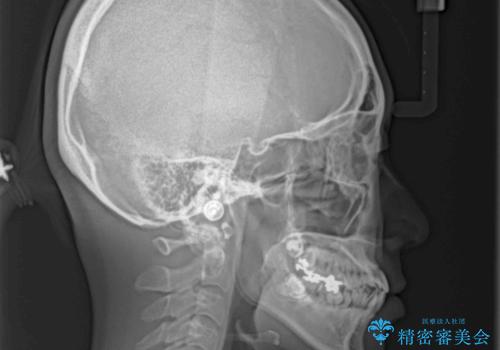

- 下顎の歯が舌側に倒れていることと、前歯の咬み合わせの不具合を気にして来院された患者様です。

受け口傾向の口元であるため、下顎左右小臼歯各1歯を抜歯して歯列を整えることとしました。

前歯には治療中の仮歯が装着されていたため、矯正治療後にオールセラミッククラウンにて補綴治療を行うこととしました。